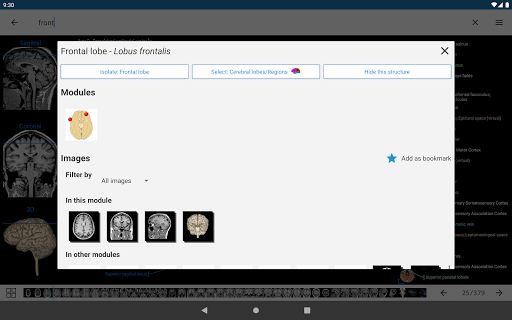

*Vista detallada mejorada de partes anatómicas para una identificación más fácil en imágenes del módulo actual y otros.

-Dentro de la vista de detalles de una estructura anatómica , un alfiler ahora señala la estructura relacionada en todas las imágenes presentes

También toque directamente en la imagen para navegar a la imagen presentada en ese módulo

- "Filtrar por", en la vista de detalles ahora puede filtrar las imágenes que contienen la estructura anatómica por modalidad

- "Filtrar por", en la vista de detalles ahora puede filtrar las imágenes que contienen la estructura anatómica por modalidad